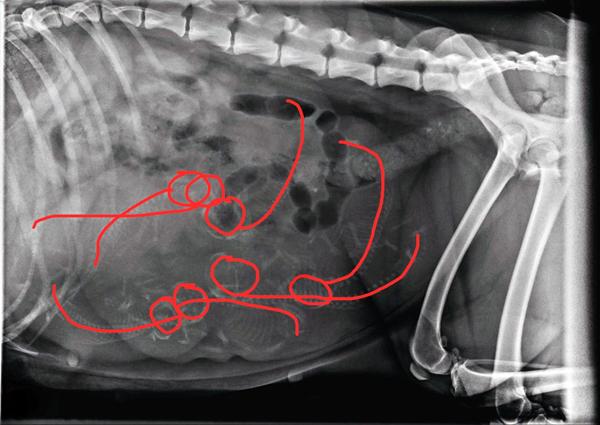

Nu sidder jeg så med billederne fra røntgen, og studser over antallet af små vidundere. Jeg har siddet og leget lidt med kontrasterne, kigget efter kranier, rygrad, ribben.. Sammensat, gættet, kørt lidt frem og tilbage. Er kommet frem til mit umiddelbare gæt - men hvad er jeres?

Mht antallet, så var dyrlægens gæt 6, måske 7. Præcis som Malene har vist, med de to øverst til venstre, hvor deres kranier overlapper hinanden. Det var lidt lettere at se efter jeg fik rodet med kontrasten herhjemme, end på det lysere billede fra dyrlægen.

jeg er også på de 7 stk